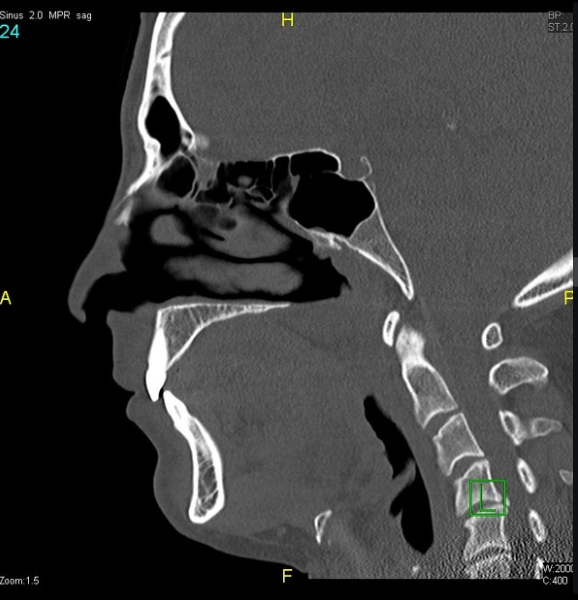

Результаты дополнительного исследования: заднее нёбное пространство сильно сужено, вплоть до полного исчезновения, и составляет около 0,1 см. Нёбный язычок и мягкое нёбо выглядят необычно длинными и слегка утолщенными. Задняя стенка глотки слегка утолщена.

Предварительный диагноз: Синдром обструктивного апноэ сна (СОАС).